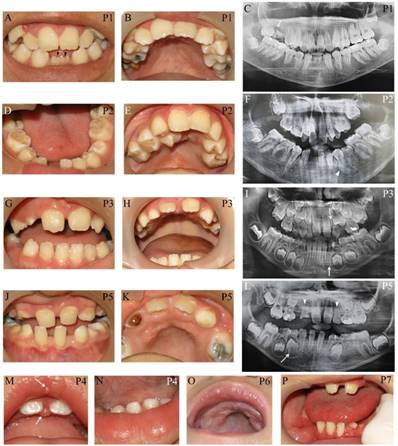

Apart from typical facial features, the common craniofacial phenotype of our KS patients included tooth absence, malocclusion, micrognathia, and high-arched palate/cleft palate. Abnormal tooth size and shape, deviated tooth roots, lip pits and nodules, and dental caries were frequently found. Patient 1 at 13 years presented pitted primary mandibular incisors, malocclusion, high-arched palate, bifid uvula, retained roots of maxillary right first molars with a periapical infection, and absence of four permanent mandibular incisors and maxillary right third molar (Figure 2A-C). Patient 2 at 15 years showed cleft soft palate, short uvula, pits and nodules on the lower lip, severe tooth crowding, root dilaceration, delayed tooth development, and absence of multiple permanent teeth including maxillary four lateral incisors, one mandibular central incisor, three second premolars, and two second molars (Figure 2D-F). Patient 3 at 7 years had high-arched palate and absence of permanent maxillary left lateral incisor and mandibular left canine (Figure 2G-I). Patient 5 at 9 years demonstrated spaced dentition, high arched palate, short truncated roots of maxillary lateral incisors, malalignment of unerupted mandibular right first premolar, and absence of multiple permanent teeth including four lateral incisors, four canines, maxillary first premolars, and mandibular left second premolar. Third molars were not present (Figure 2J-L). Patient 4 at 14 months showed the nodules on the upper lip and gingiva, cleft palate, and six primary teeth including two maxillary central incisors, and four mandibular incisors (Figure 2M, N). High-arched palate was observed in Patient 6 at 2 years (Figure 2 O). Patient 7 at 7 years had only 6 permanent teeth and severe hypoplasia of alveolar ridge (Figure 2P). The number of tooth agenesis ranged from two to eleven permanent teeth excluding the third molars. The most common missing teeth were lateral incisors and second premolars. The clinical, radiographic, and laboratory manifestations including physical features, medical conditions, craniofacial and oro-dental characteristics were summarized in Table 1 and Figure 2.

Figure 2

Oro-dental photographs and panoramic radiographs of the patients. (A-C) Patient 1 at 13 years presents pitted primary mandibular incisors (arrowheads), malocclusion, high-arched palate, absence of four permanent mandibular incisors and maxillary right third molar, retained roots of maxillary right first molars with a periapical infection (arrow). (D-F) Patient 2 at 15 years shows cleft soft palate, severe tooth crowding, root dilaceration (arrowhead), delayed tooth development, and absence of multiple permanent teeth including maxillary four lateral incisors, one mandibular central incisor, three second premolars, and two second molars. (G-I) Patient 3 at 7 years has high-arched palate and absence of permanent maxillary left lateral incisor and mandibular left canine (arrows). (J-L) Patient 5 at 9 years demonstrates spaced dentition and high arched palate. Radiograph reveals the truncated roots of maxillary lateral incisors (arrowheads) and malalignment of unerupted mandibular right first premolar (arrow), and absence of multiple permanent teeth including four lateral incisors, four canines, maxillary first premolars, mandibular left second premolar. Third molars were not present. (M, N) Patient 4 at 14 months shows the nodules on the upper lip and gingiva (arrows), cleft palate, and six primary teeth including two maxillary central incisors and four mandibular incisors. (O) High-arched palate is observed in Patient 6. (P) Patient 7 at 7 years has only 6 permanent teeth and severe hypoplasia of alveolar ridge. P, patient.